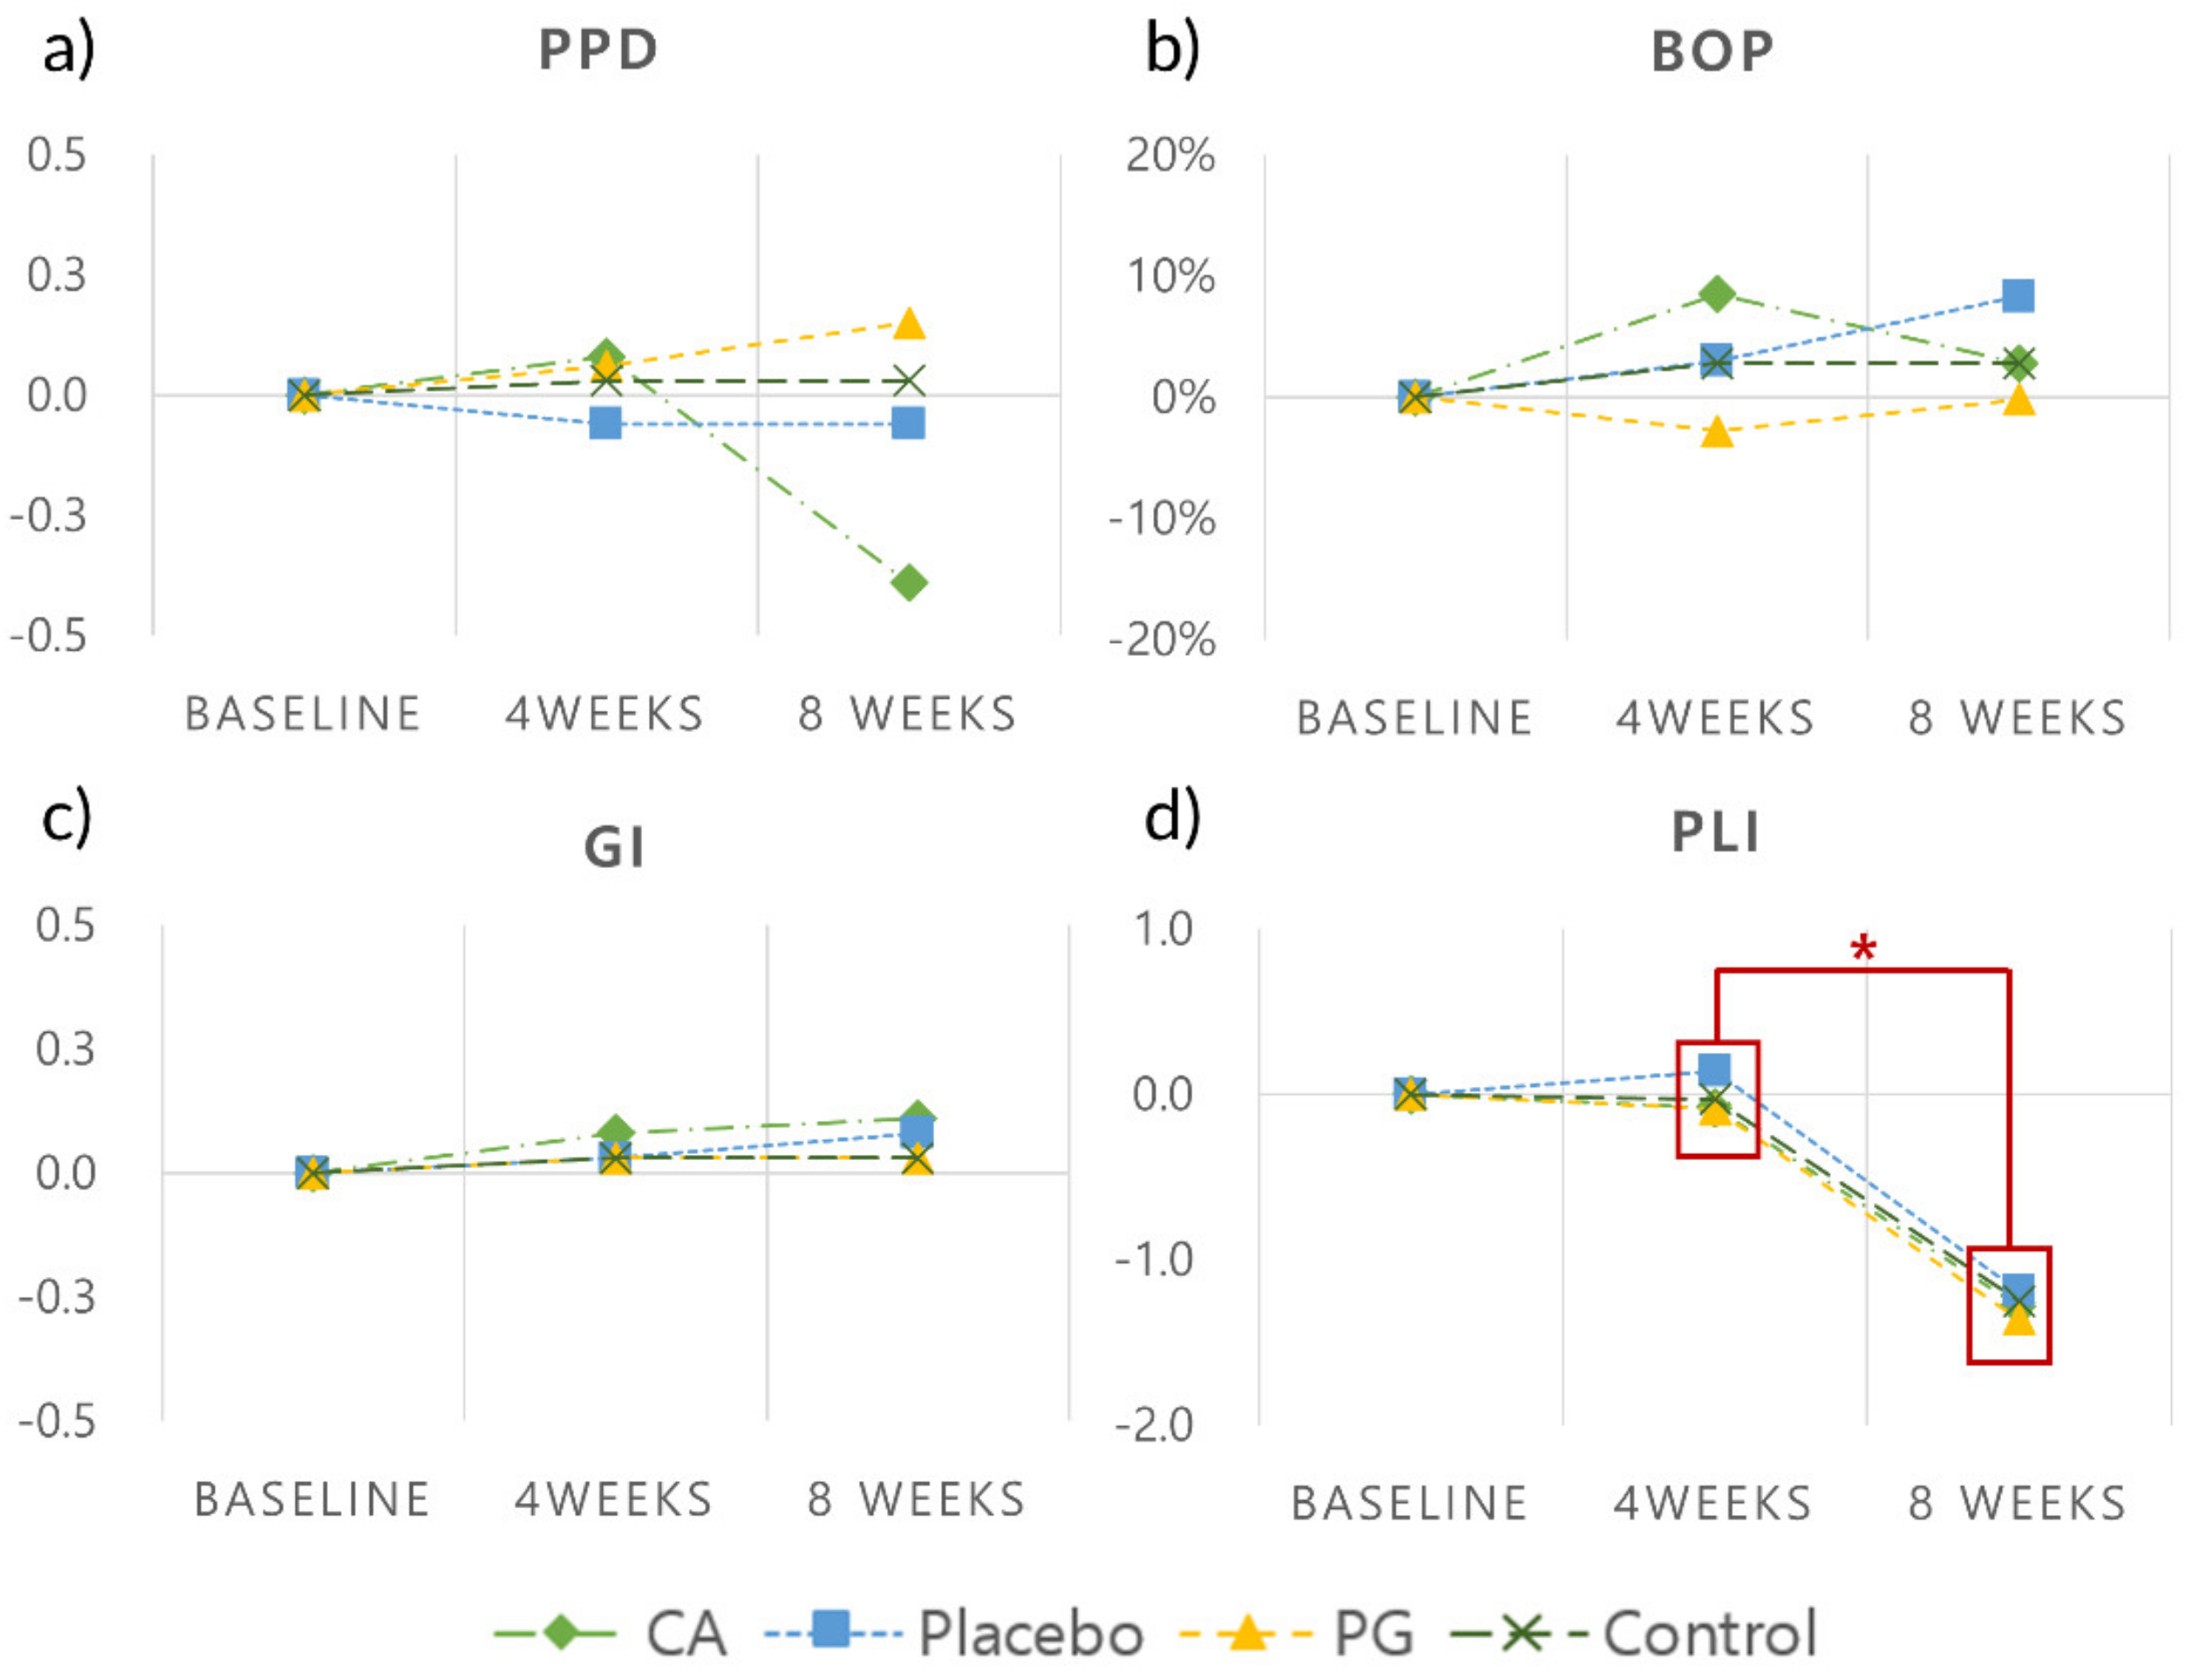

3.2. Clinical Findings